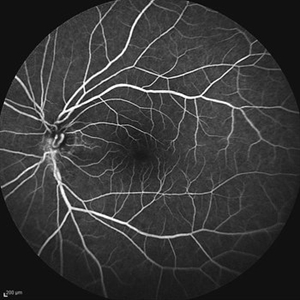

Behcet's Disease Behcet's DiseaseMar 13 2013 by Hamid Ahmadieh, MD Early phase FA of the left eye of a 23-year-old man with retinal vasculitis due to Behcet's disease . Photographer: Solmaz Shahmohammad, Negah Eye Center, Tehran Imaging device: Heidelberg Spectralis Condition/keywords: retinal vasculitis